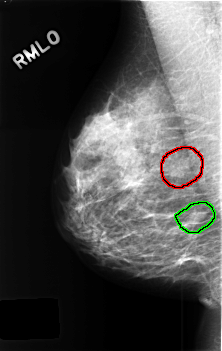

C_0437_1.RIGHT_MLO

RIGHT_MLO LINES 4560 PIXELS_PER_LINE 2880 BITS_PER_PIXEL 12 RESOLUTION 50 OVERLAY

FILE: C_0437_1.RIGHT_MLO.OVERLAY

TOTAL_ABNORMALITIES 2

ABNORMALITY 1

LESION_TYPE MASS SHAPE FOCAL_ASYMMETRIC_DENSITY MARGINS N/A

ASSESSMENT 3

SUBTLETY 3

PATHOLOGY BENIGN_WITHOUT_CALLBACK

TOTAL_OUTLINES 1

BOUNDARY

ABNORMALITY 2